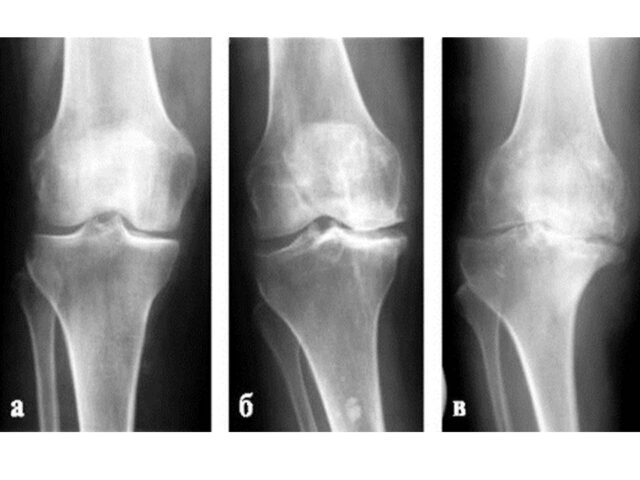

Najbolji i najjači lekovi za lečenje artroza razvijeni su u obliku injekcija koje se daju u obolele zglobove. Kao osnovni lek sadrže hijaluronsku kiselinu. Injekcije sa hijaluronskom kiselinom se u svetu, u terapiji artroza, koriste već nekoliko decenija. Ti lekovi kod srednje teških artroza kolena i kukova mogu da pomognu da se ublaže bolesnikove tegobe i da dodje do izvesnog oporavka. Bolji lekovi u konzervativnom lečenju u zvaničnoj medicini trenutno ne postoje.

Rana dijagnoza bolesti prvi je preduslov za dobru kontrolu bolesti i uspešno lečenje. Za postavljanje dijagnoze ali i praćenje toka i lečenje reumatskih bolesti –